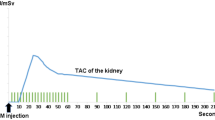

Twenty-four background-corrected renogram TACs using 99mTc-labelled mercapto-acetyl-triglycine (MAG3) with a unilateral obstructive pattern and six normal control renograms TACs were studied. Optimised computed models of each curve were constructed using specialised software (ModelMaker, Cherwell Scientific) and using the Marquardt Least Squares method. Following optimisation to the TAC of each target renogram, the afferent flow rate parameters were calculated.

Following optimisation of models, afferent flow rate parameters, expressed as arbitrary units, (mean 0.15, SD 0.06) in acutely obstructed kidneys, were typically reduced in comparison with those of normal kidneys (mean 0.44, SD 0.04). (Paired t test; P < 0.005). By contrast, this reduction in afferent flow rate parameter was greater than the reduction in differential tracer uptake for the obstructed kidney (divided renal function of the obstructed group; mean 0.3, SD 0.14 compared with the control group; mean 0.45, SD 0.05 (P < 0.05).

Optimised modelling of TACs of obstructed renograms is feasible and may provide a more sensitive index of parenchymal dysfunction in early obstruction than comparing divided renal tracer uptake.